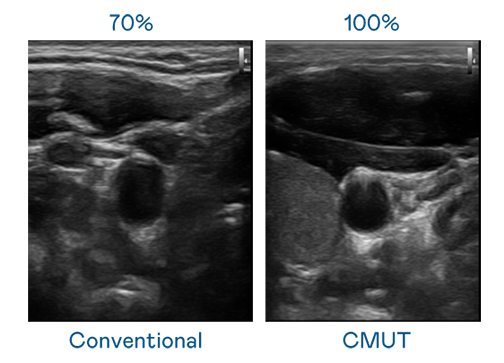

CMUT 技术是一种用电容式微机电元件来产生超音波讯号的技术。与传统 PZT 压电式技术相比,CMUT 频宽增加 30%,更宽频的超音波讯号让影像解析度大幅提升,是实现高影像品质医疗超音波扫描、促进精准医疗发展的关键技术。

超音波影像的解析度高低,首先取决于探头能发出的讯号频宽。来利国际w66 CMUT 可提供高清晰的超音波讯号,提供高频宽、高灵敏度、影像纹理细节更高的超音波影像,协助医护人员缩短影像判读时间及利用精准的医疗影像进行诊断。